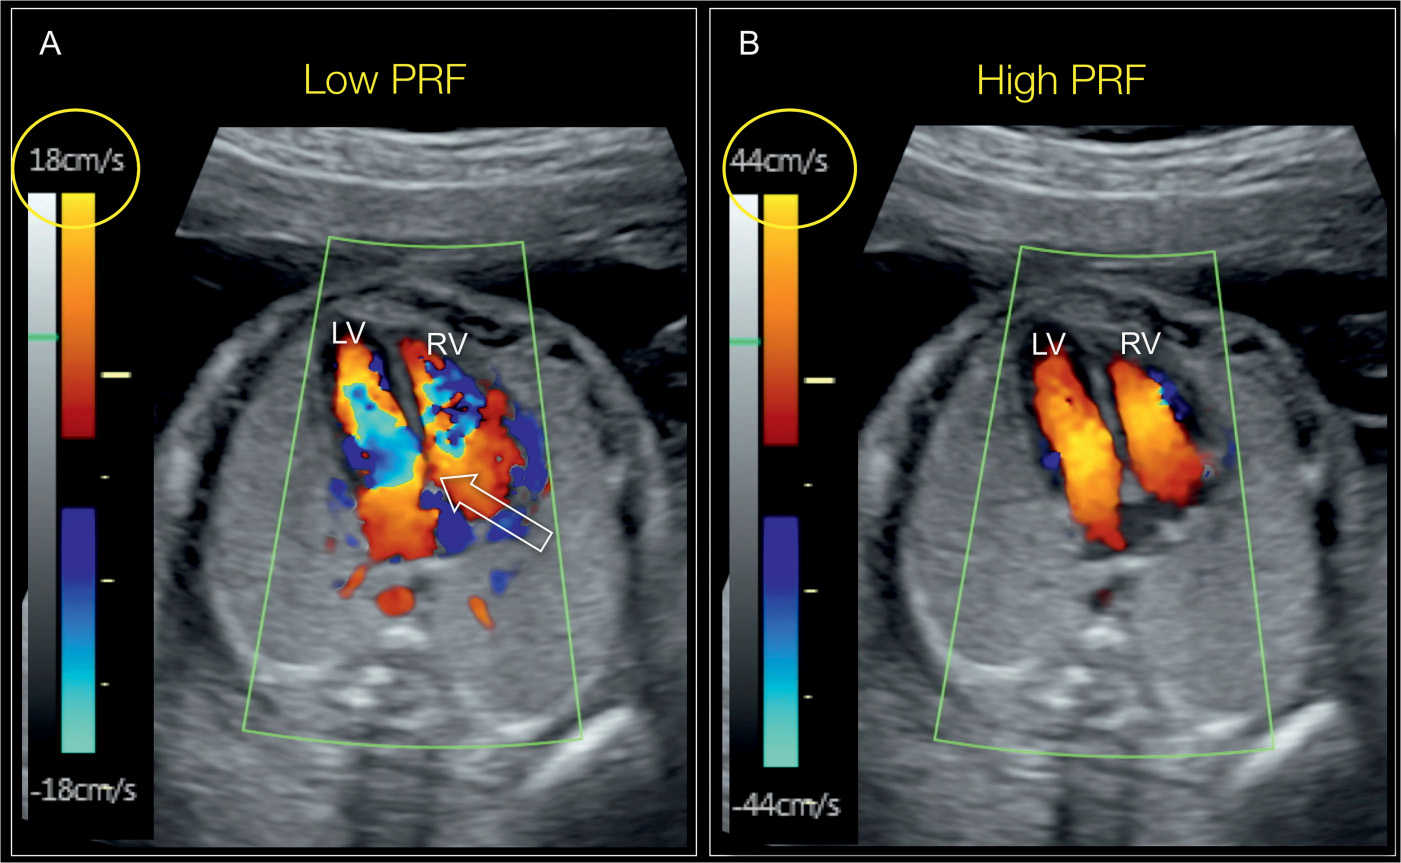

Blue color implies velocities (movement) away from the transducer and red color implies velocities (movement) towards the transducer. The ultrasound’s computer measures the speed and direction of blood flow through the heart and blood vessels. Color doppler is a useful adjunct to cw doppler in the. An echocardiogram may use several special types of echocardiography, as listed below: An echocardiogram.

This, the simplest type of echocardiography, produces an image that is similar to a tracing. Color doppler is especially useful in the diagnosis and quantitation of valvular regurgitation, and in the detection of intracardiac shunts. These measurements may be demonstrated in color or black and white. Blue color implies velocities (movement) away from the transducer and red color implies velocities.